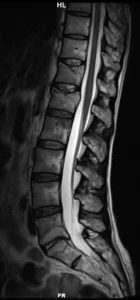

Resonancia Magnetica

RM sagital en secuencias T2 (1), T1 (2) y STIR (3). La RM permite establecer qué se trata de un trauma reciente por la presencia de edema óseo (hiperintenso en secuencias ponderadas en T2, hipointenso en T1). Es el método de elección para evaluar la médula espinal, el cono y las raíces nerviosas. Adicionalmente, muestra la patología degenerativa discal y vertebral.

Qué agrega la RM (y cuándo es clave):

- Confirma edema medular óseo (fractura aguda) y ayuda a diferenciar fracturas recientes vs crónicas.

- Valora lesión ligamentaria (complejo posterior) y tejidos blandos paravertebrales.

- Evalúa médula/conus/cauda y hematoma epidural si hay síntomas neurológicos.